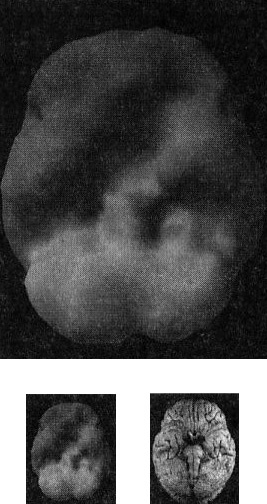

Когда мозг работает правильно, у вас все хорошо Когда мозг не в порядке, в жизни начинаются неприятности Именно мозг определяет эффективность вашей жизни. Этот принцип выглядит простым, но на самом деле он достаточно неоднозначный и может вызвать тревожность. Основная идея заключается в том, что мозг должен функционировать оптимально. Когда он работает правильно, вам легче оставаться эффективным родителем, ребенком, партнером, другом, коллегой, менеджером или общественным деятелем. Когда мозг функционирует правильно, вы имеете полный доступ к своему истинному Я. С другой стороны, если мозг болен, начинаются трудности в работе, отношениях, наедине с собой и в компаниях. Становится труднее проявлять свои лучшие качества и сильные стороны, нередко люди действуют вопреки своим ценностям, целям и представлениям о нравственности. Принцип 2 Когда мозг работает правильно, у вас все хорошо. Когда мозг не в порядке, в жизни начинаются неприятности Я вывел этот принцип в результате интерпретации сотен томограмм моих пациентов, поскольку не только читаю сканы, но и напрямую работаю с людьми и их семьями, изучаю историю их жизней. Уже в самом начале моей работы с томографией стало очевидно, что существует зависимость между качеством функций мозга на сканограммах и умением моих пациентов принимать решения, ставить цели и поддерживать отношения. Анализируя снимки, я стал размышлять о разнице между двумя типами поведения, которые я называю волевым поведением (управляемым силой воли) и мозговым поведением (управляемым неконтролируемыми импульсами мозга). Реализовывать команды силы воли возможно только при здоровом мозге, поскольку лишь он позволяет людям делать осознанный выбор и в любой ситуации действовать себе во благо. Волевое поведение продуктивно, оно способствует достижению целей, которые вы сами поставили. Например, приняв решение поступить в медицинский институт, человек должен очень усердно учиться, чтобы выдержать сложные экзамены. Прежде чем объяснить, что такое «мозговое поведение», я хочу сделать небольшое отступление, чтобы рассказать о томографии, которую мы проводим в наших клиниках. Она называется ОЭКТ — однофотонная эмиссионная компьютерная томография — и относится к области ядерной медицины, то есть для оценки кровообращения и схем активности мозга используются крошечные дозы радиоизотопов. Сканограммы ОЭКТ отличаются от типичных анатомических снимков МРТ и КАТ, которые показывают строение мозга. ОЭКТ показывает только степень активности разных областей мозга — то, как он работает. Результаты сканов ОЭКТ очень легко интерпретировать. Нужно посмотреть на области мозга, которые работают хорошо, области, которые функционируют чересчур активно («перегреты») и на недостаточно активные области. Затем мы сравниваем изучаемый скан с большой базой данных здоровых и абнормальных томограмм. В этой книге используют трехмерные снимки мозга двух видов. Первый — это трехмерные снимки поверхности, которые фиксируют верхние 45 % активности мозга. На них показано кровообращение в коре мозга и подкорковых областях. По этим снимкам мы определяем области нормального кровообращения и области со сниженным доступом крови. С помощью таких томограмм выявляют инсульты, травмы и ущерб от наркотиков. Снимок здорового мозга должен показать ровную симметричную активность по всей поверхности коры мозга (рис. 2.1 и 2.2). Трехмерное изображение поверхности здорового мозга ОЭКТ (вид поверхности сверху и снизу) Рис. 2.1 Вид сверху Полная симметричная активность ![]() Рис. 2.2 Вид снизу Полная симметричная активность ![]() Сниженная активность выглядит на подобных сканах как дыра или вмятина. Эти «дыры» и «провалы» не означают, что активность мозга в этих местах совсем на нуле, она просто снижена, так как компьютер настроен показывать только верхние 45 % активности. Все, что меньше этого значения, выглядит как дыра или вмятина. Порог в 45 % выбран, поскольку он соответствует двум стандартным отклонениям от нормы [1] и, согласно нашим данным и данным других исследователей, является оптимальным для диагностических целей. Второй тип томограмм — это трехмерные функциональные снимки, в которых компьютер сначала вычисляет среднюю активность мозга, а затем показывает верхние 15 % активности. Они помогают увидеть гиперактивные области, что полезно в диагностике припадков, разных типов тревожности и депрессии. Здоровый трехмерный функциональный снимок (рис. 2.3 и 2.4) должен показывать активность (белым цветом) в задней части мозга (мозжечке) и визуальной, или затылочной, коре и среднюю активность в остальных местах (показано сеткой). Трехмерное изображение функциональной активности здорового мозга ОЭКТ (вид поверхности сверху и снизу) Рис. 2.3 Вид сверху ![]() Рис. 2.4 Вид сверху ![]() Примечание: В тексте книги будут использоваться иконки, которые помогут читателю понимать сканограммы и увидеть их отличия от нормы. Рис. А состоит из двух иконок: трехмерного изображения поверхности здорового мозга, вид сверху; и модели мозга с той же самой перспективы. ![]() Рис. Б показывает трехмерный снимок поверхности здорового мозга, вид снизу, а нижняя иконка — это модель мозга с той же перспективы. ![]() Рис. В показывает трехмерную картину активности здорового мозга, вид сверху, а ниже показан мозг в этой проекции. ![]() |